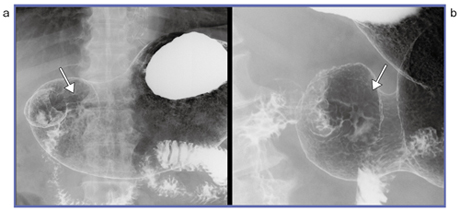

●症例2(図2)

a→にいびつなバリウムの溜まりが認められる。検査後半に蠕動が激しくなり,撮影のタイミングが合いにくいため,連続撮影を行い(b),撮影像を得た症例である。

図2 症例2:連続撮影